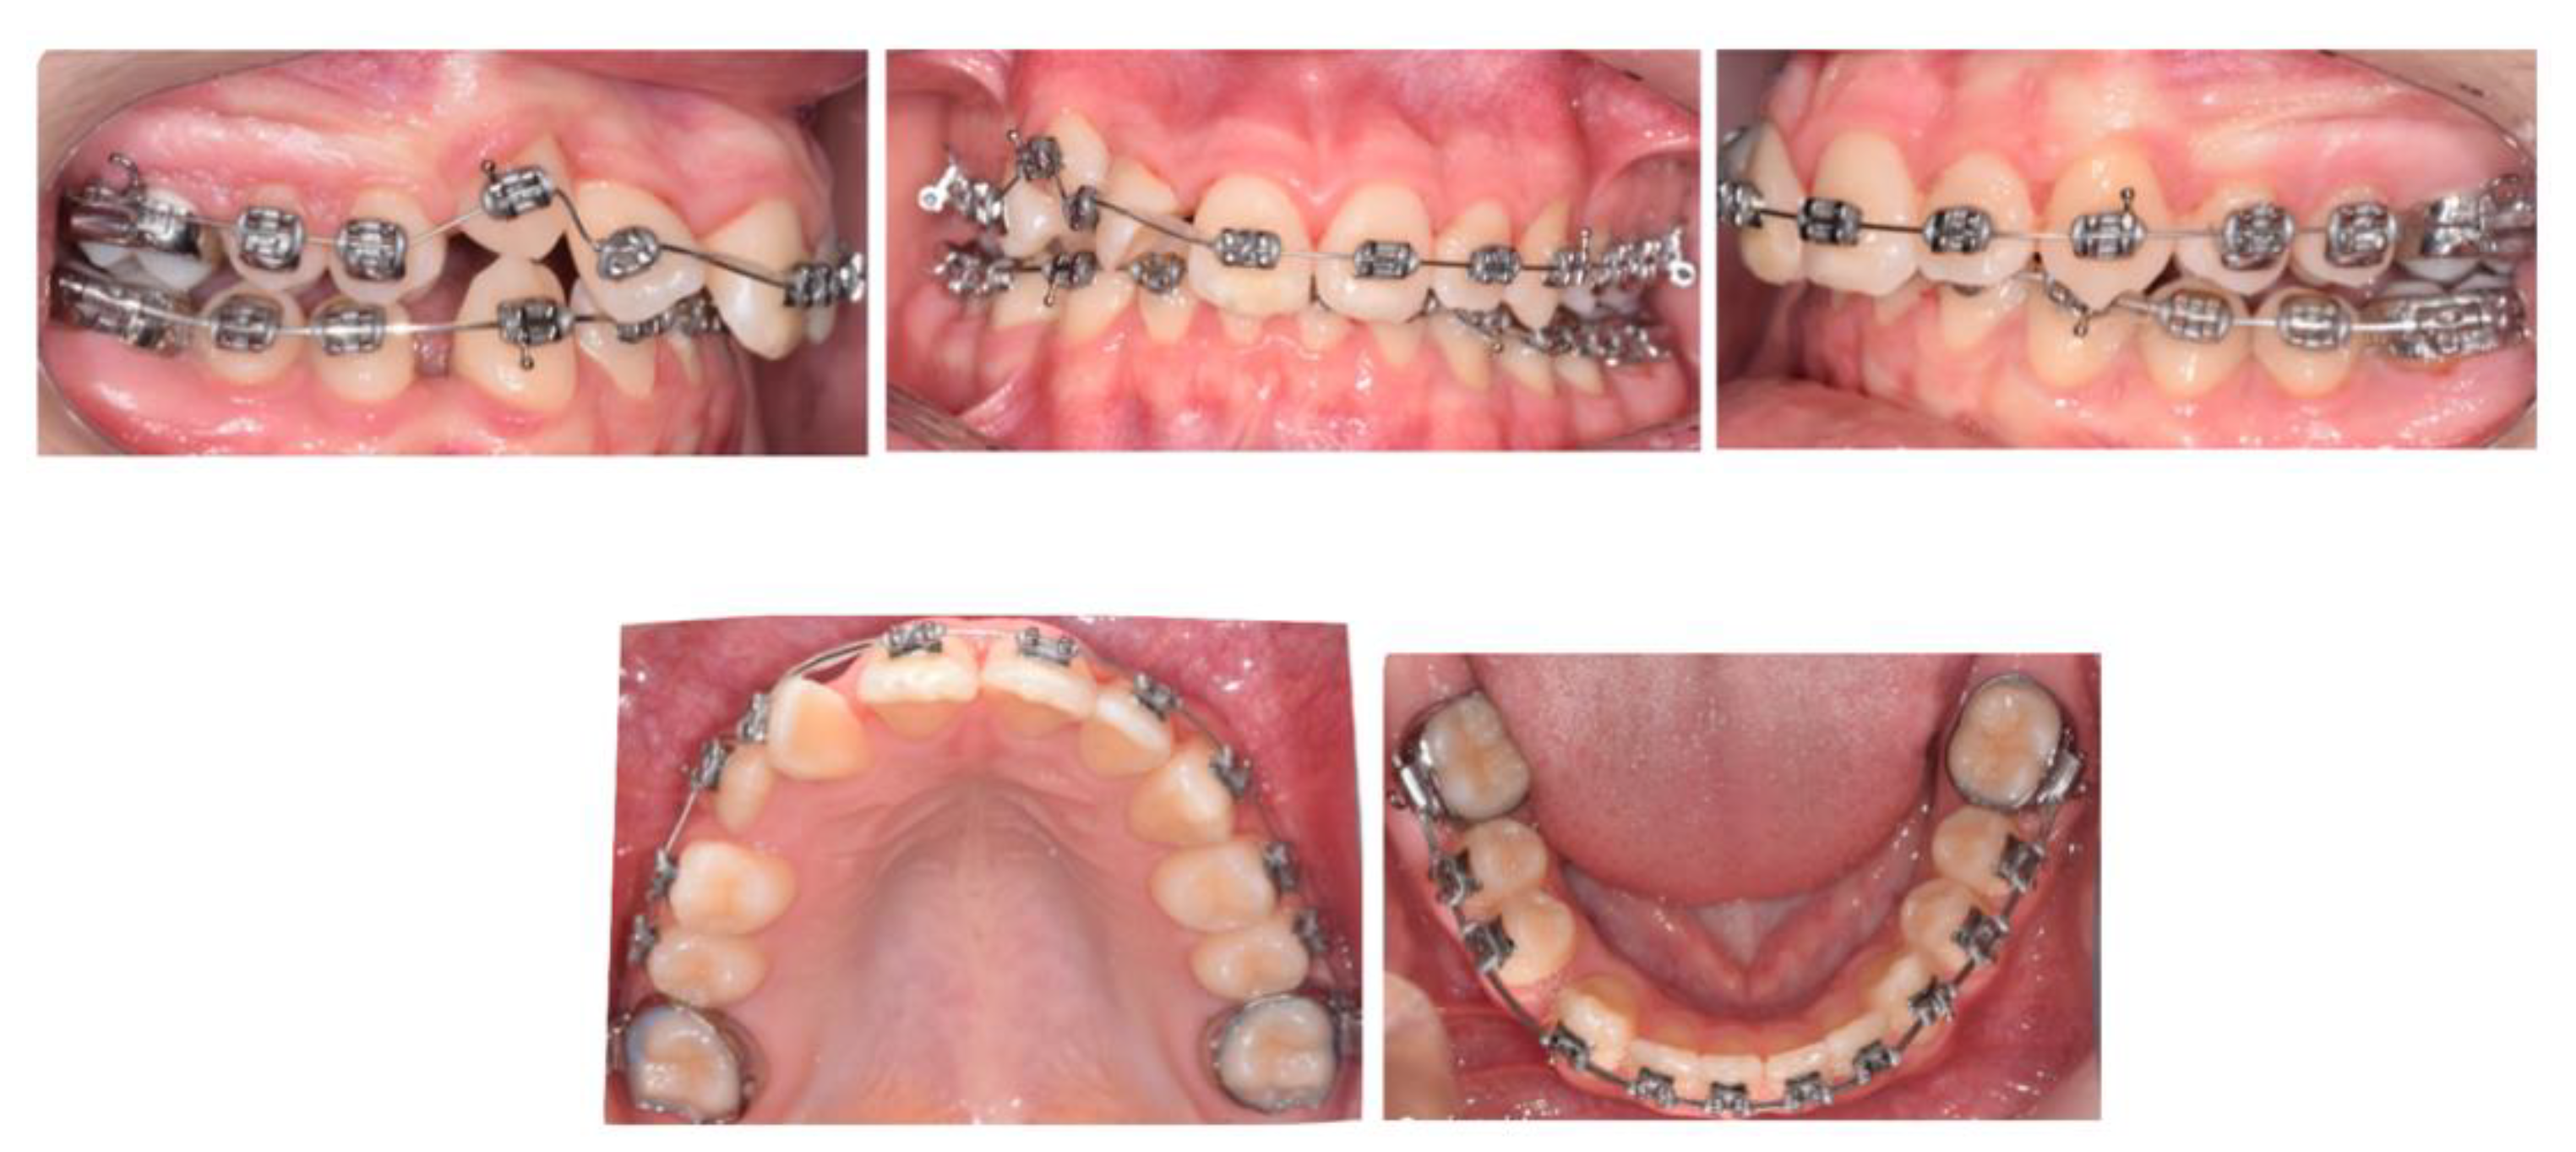

2.1. Case 1—Delayed Extraction of FPMs

Discussion

- ▪

- The upper second permanent molars were still within bone at the time of extraction;

- The OPT revealed signs of molar stacking of upper right and left second permanent molars, and distally tipped lower right and left second permanent molars reflecting posterior molar crowding;

- The distinct vertical growth pattern and presence of a steep mandibular plane, which encouraged molar mesial movement.